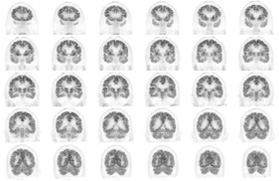

Head / Case2 : FDG

Coronal

Courtesy : Kindai University Hospital

- Imaging protocol

- Injected dose: 3.29 MBq/kg, 18F-FDG

- Uptake time: 38 minutes

- Scan time: 30 minutes